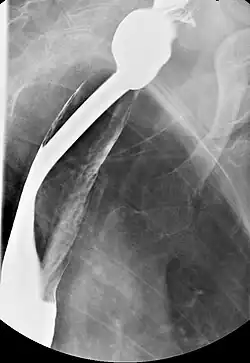

Serial contrast gastrointestinal radiography or upper-gastrointestinal endoscopy may reveal the presence of esophageal webs.

Barium esophagography and videofluoroscopy can aid in detecting esophageal webs. Esophagogastroduodenoscopy allows for the visual confirmation of these webs, which are caused by subepithelial fibrosis.